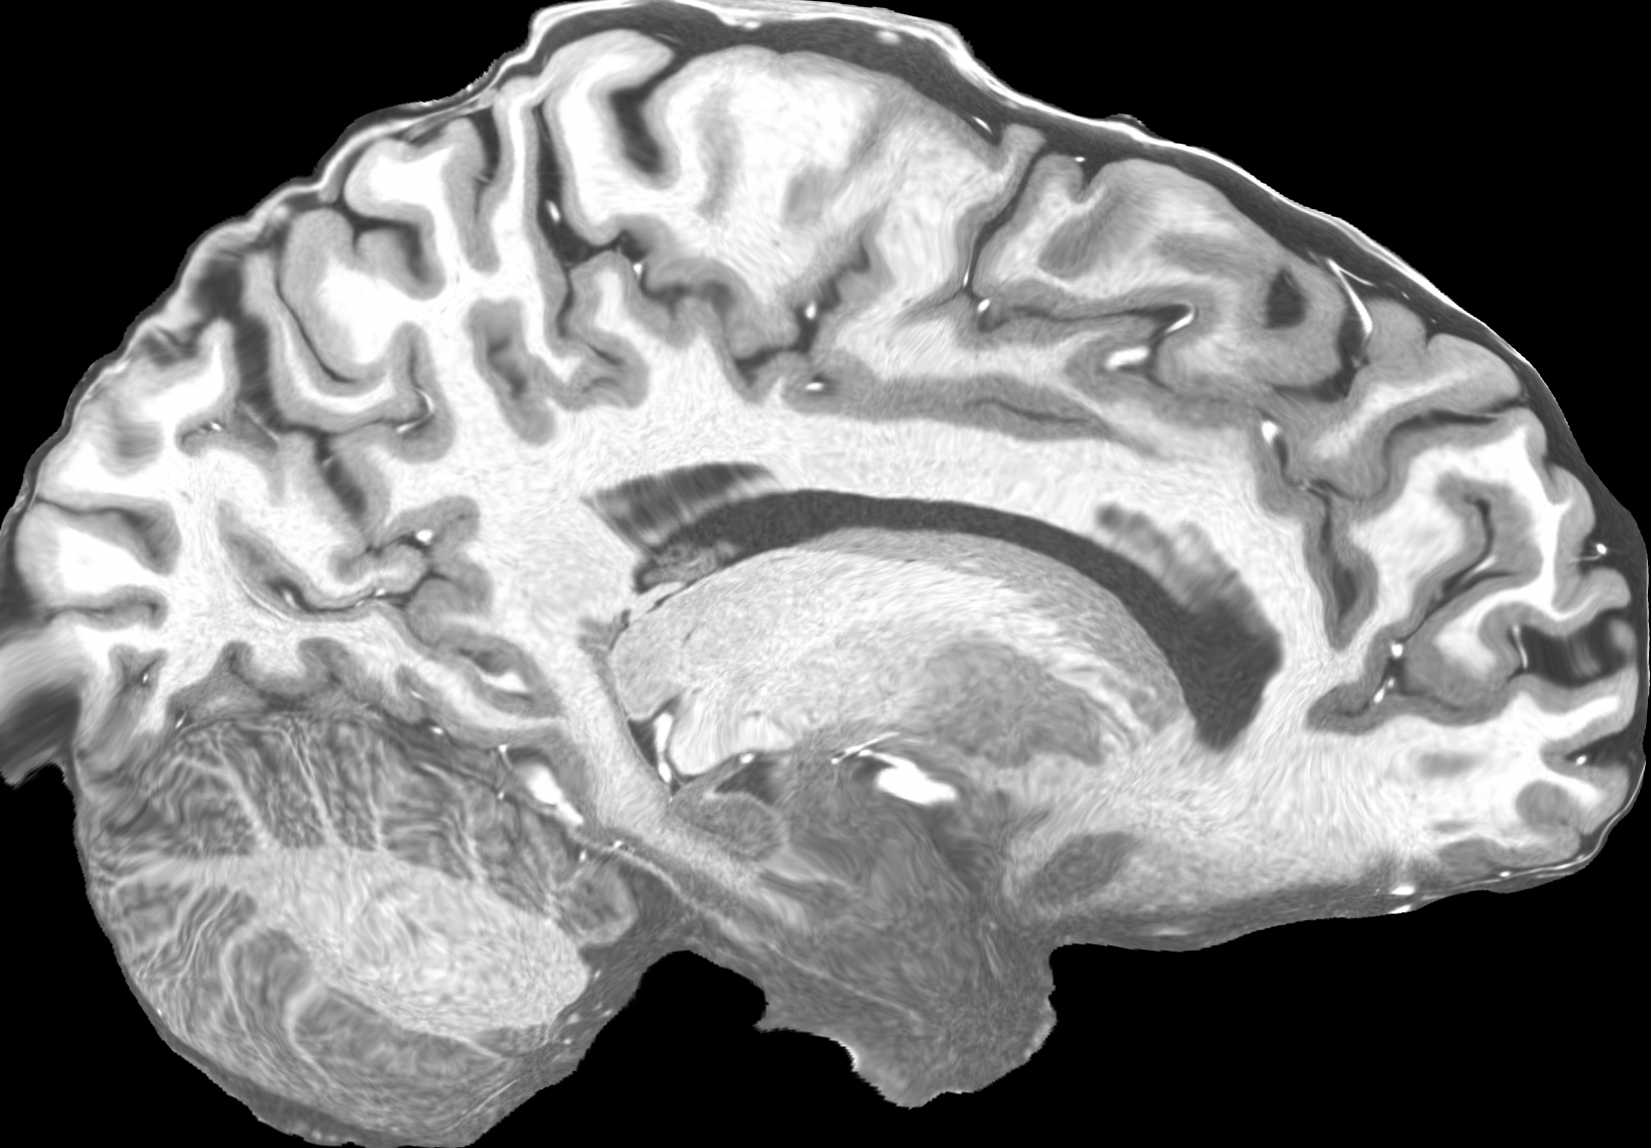

4.2 Registration to a 100 micron ex-vivo brain MRI volume

To showcase the efficacy of our method on real large scale images, we register a 250 in-vivo MRI image (Lüsebrink et al., 2017) to a 100 ex-vivo FLASH human brain volume (Edlow et al., 2019). This represents an inverse problem with more than 11.2B optimizable parameters (compared to 20M for clinical datasets), or 44.8GB of GPU memory. The entire problem does not fit on most GPUs, necessitating distributed multimodal registration. We optimize a composite transform - affine followed by a diffeomorphic mapping; details can be found in Section E.1. Multimodal deformable registration took 58 seconds on 8 NVIDIA A6000 GPUs, which is unprecedented at this resolution. Fig. 6 shows qualitative results, highlighting the ability to register highly detailed structures such as cerebellar white matter; these structures are not visible at macroscopic scales. The resultant advantages of performing registration at this scale can allow researchers to characterize the neuroanatomy at microscopic resolutions and allow morphometric analysis of cortical layers and subcortical nuclei among other structures.